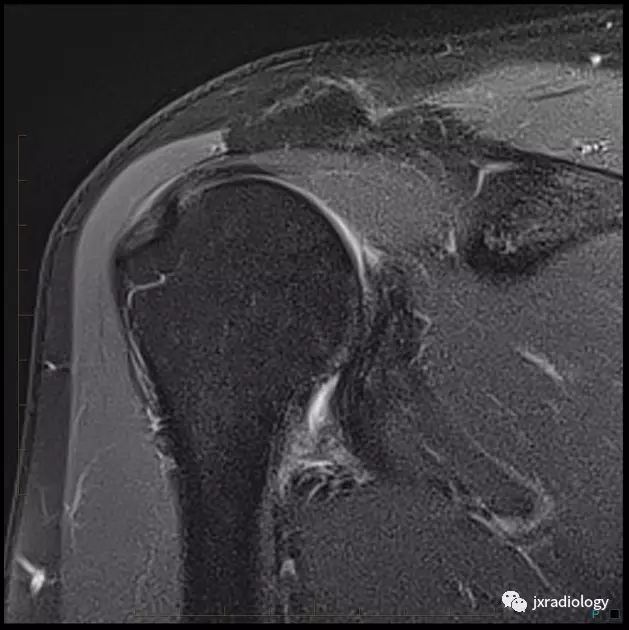

腋囊增厚纤维化(T1/T2均为低信号):

• 正常下盂肱韧带测量值<4毫米,在斜冠位上关节囊中间层面显示最好;在粘连性关节囊炎患者中,腋隐窝软组织增厚≥1.3厘米

• 关节囊增厚

• 肩袖间隙异常软组织增厚伴信号异常

• 异常软组织包绕肱二头肌腱